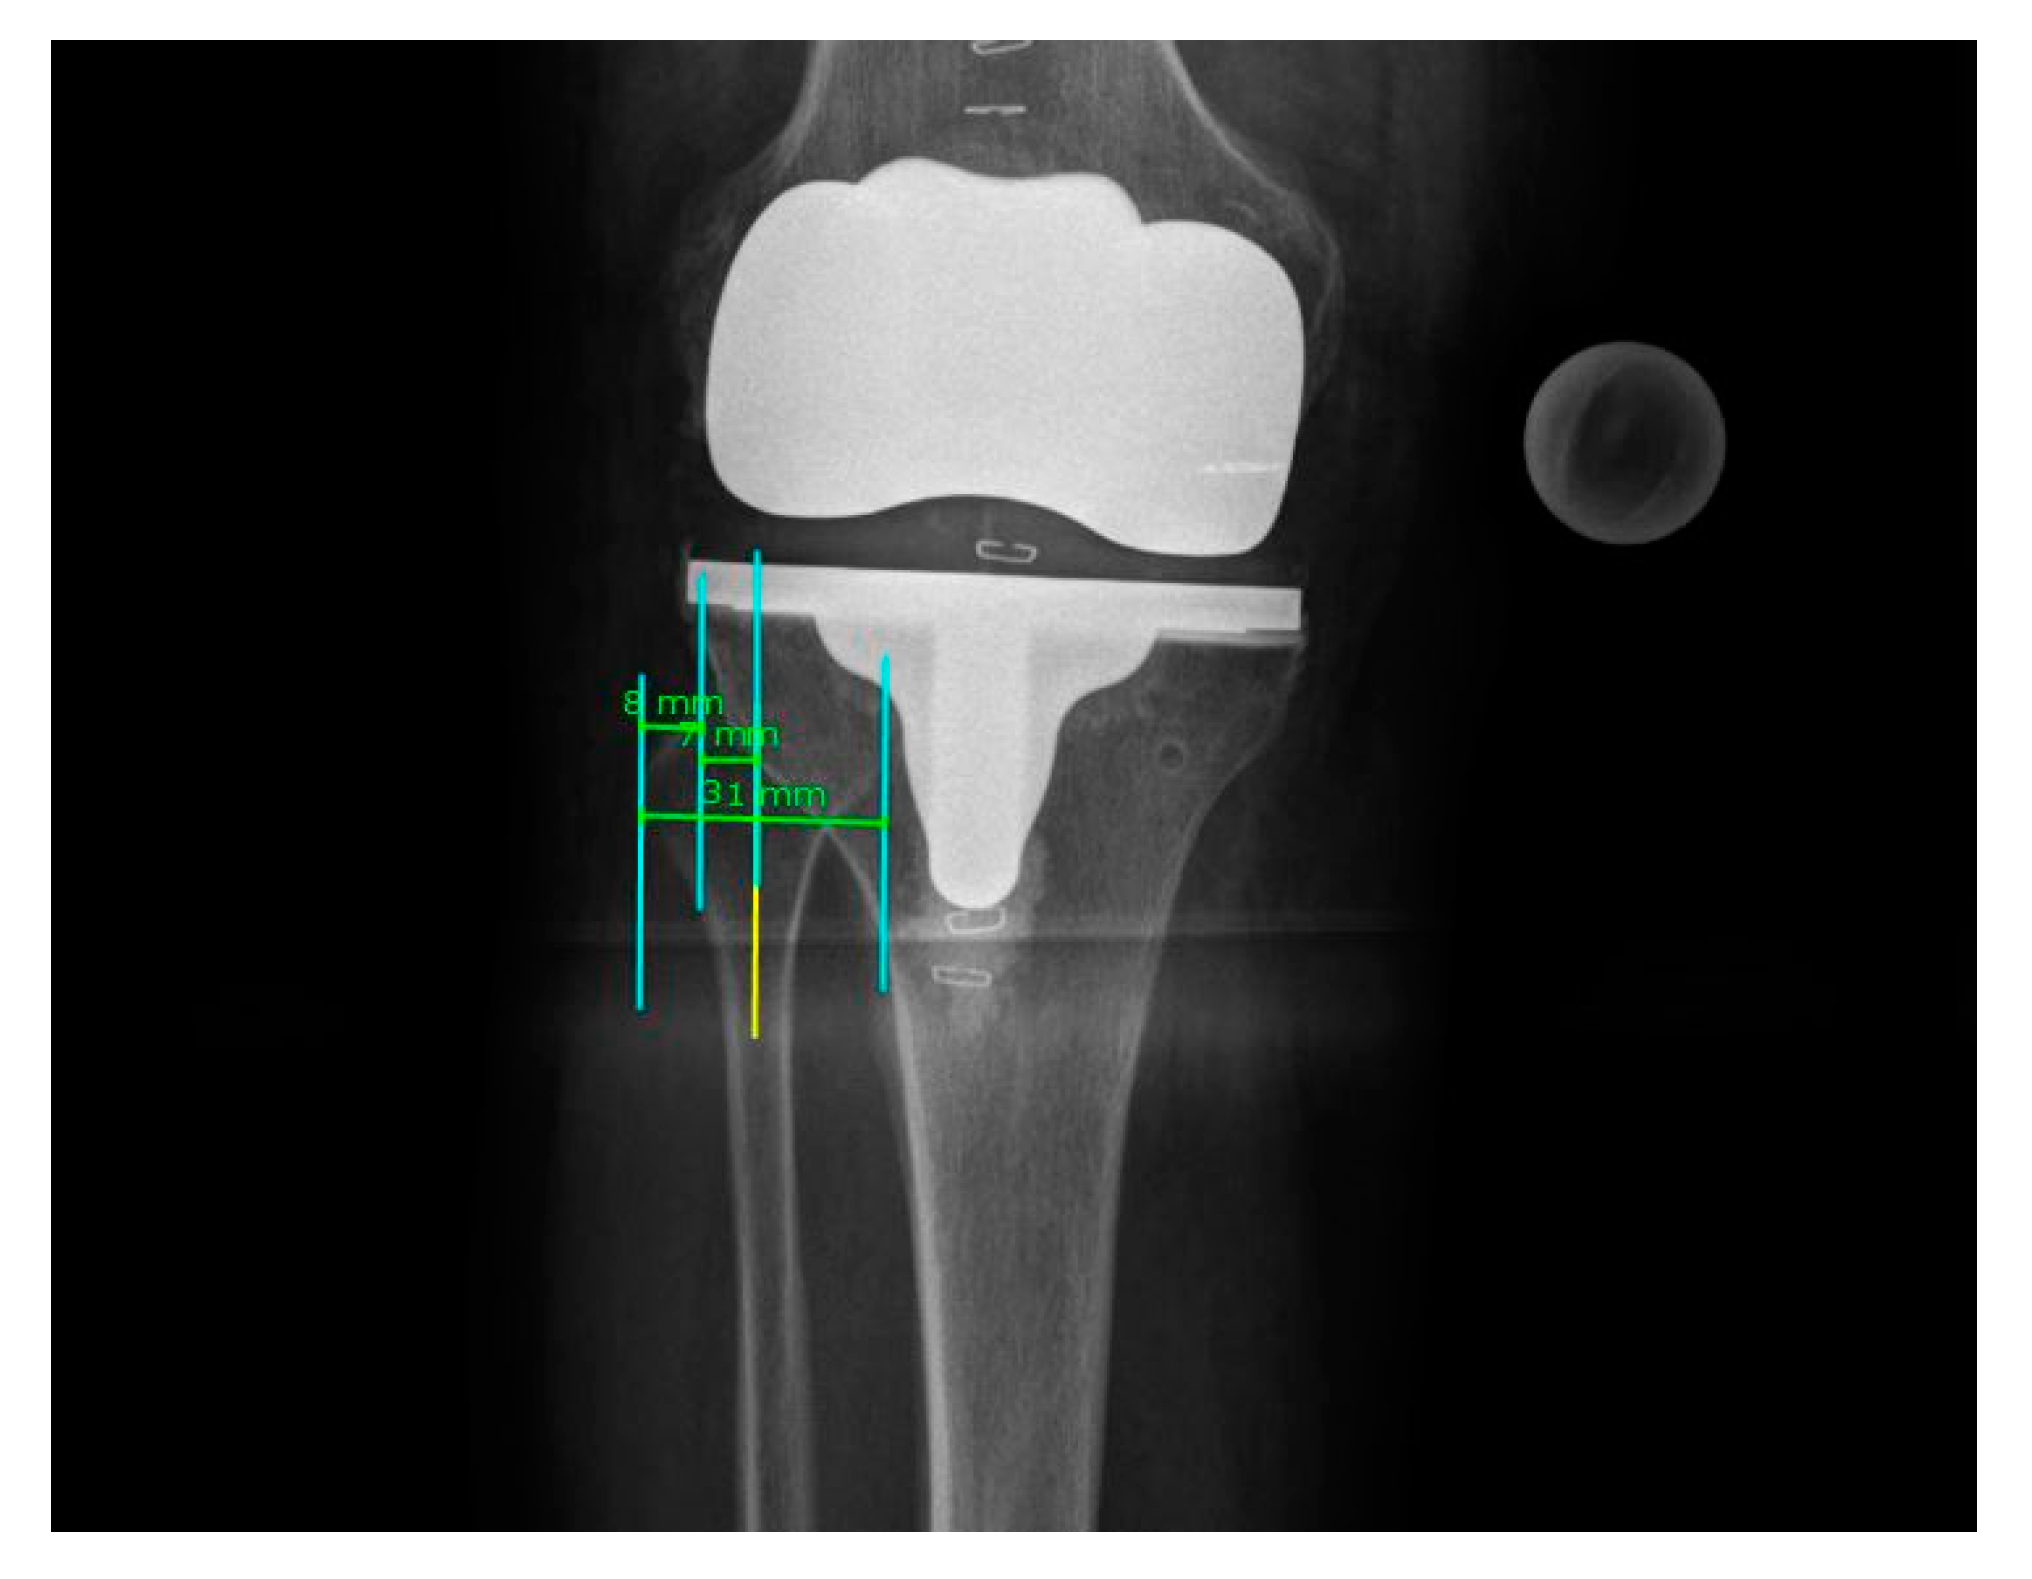

3.1. Rotational Correction